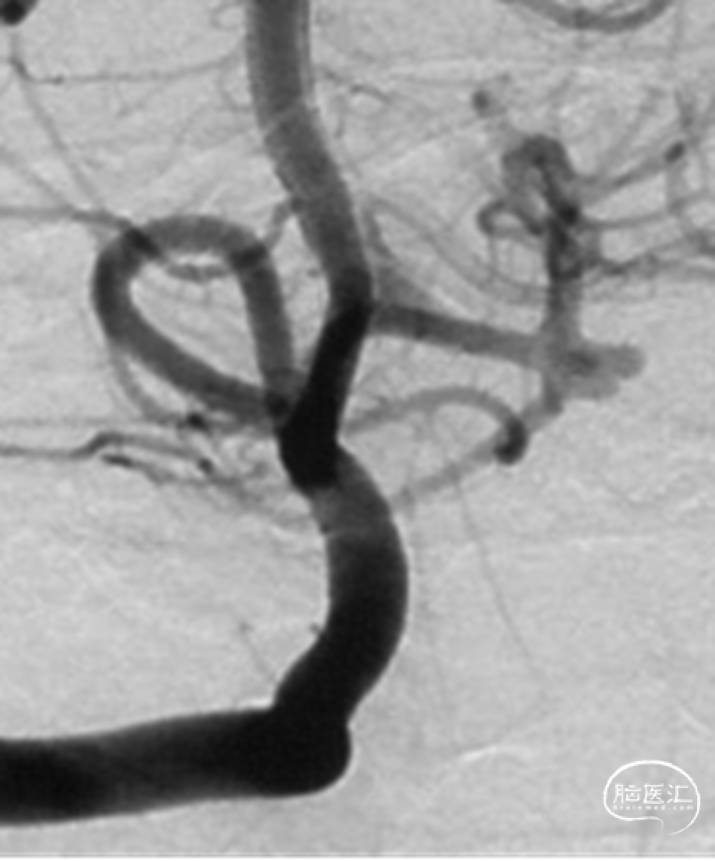

行单纯弹簧圈栓塞及载瘤动脉闭塞术。术后即刻造影提示动脉瘤不显影,载瘤动脉闭塞,侧枝代偿良好

术后情况

术后MRI未见新发脑梗,无新发神经系统阳性体征